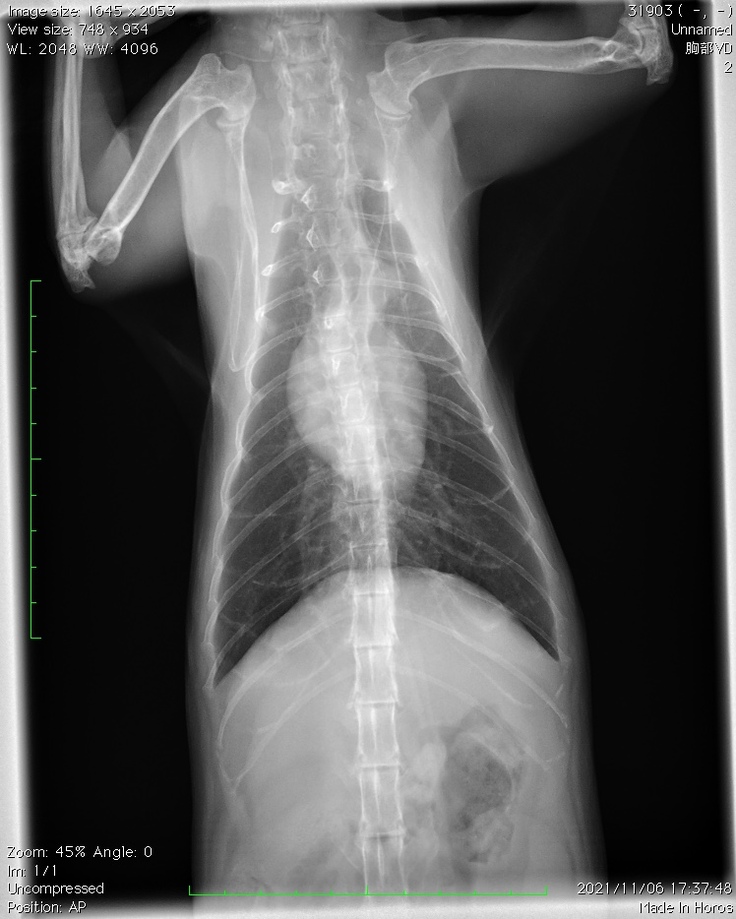

11月6日、予約しておいた腫瘍科のある動物病院にてセカンドオピニオンを受けてまいりました。

・レントゲンは撮影できるが、やはり麻酔なしでのCTやMRIは難しいということ。

・レントゲンの結果、上半身のリンパ節に転移が見られる。(ステージⅣレベル)

・肺にも薄い影があり、転移している可能性が高いとのこと。

上の画像は腸が炎症を起こしている様子だそうです。

下の画像は赤丸の中がほどんど腫瘍で『肉腫』の可能性もあるとのことでした。

レントゲン写真